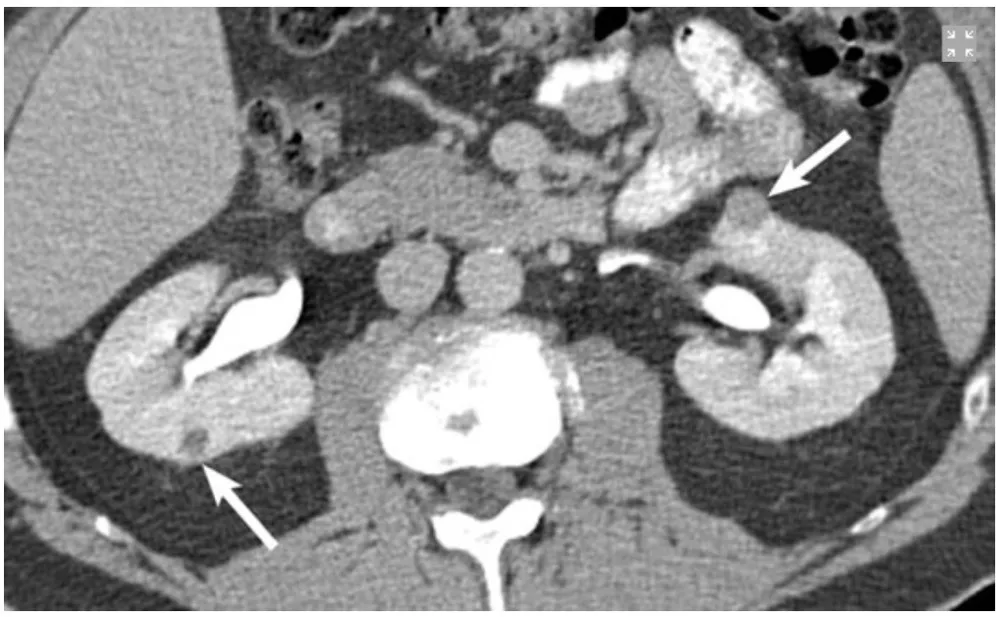

Paciente com antecedentes de carcinoma de células renais claras ressecado previamente, apresenta em exame de controle a seguintes imagens.

Na imagem 1: Um pequeno tumor exofítico com realce se projetando a partir da face anterior do polo superior do rim esquerdo (seta). Além disso, há uma lesão de 4 mm na face posterior do rim direito. Paciente foi submetido à enucleação cirúrgica da lesão renal esquerda. O tumor renal direito foi tratado com ablação por radiofrequência.